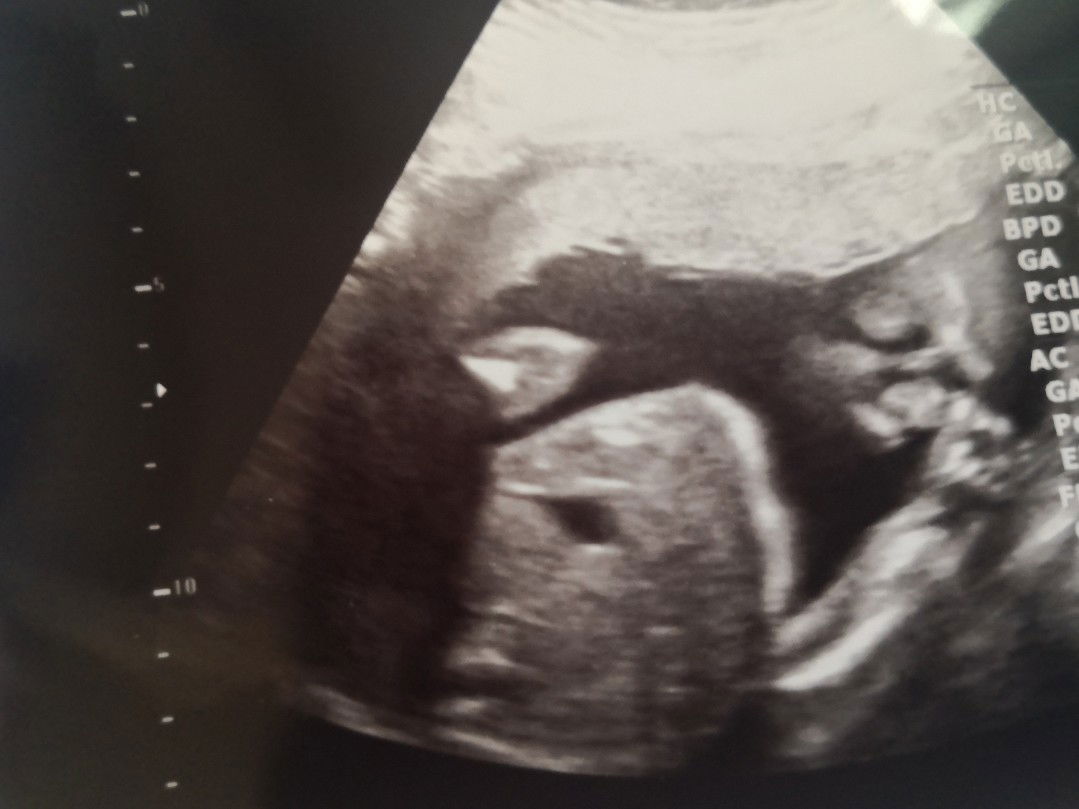

แวะดูหน้าลูกสาว

หมอบอกลูกสาวอวบอยู่นะ สมบูรณ์แข็งแรงดี ยิ้มหน้าบานทั้งอิแม่ อิพ่อเลย #23w#